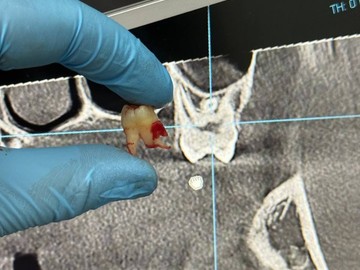

Атравматичное удаление зубов – наиболее безболезненная и щадящая процедура, которая практически не травмирует десну и костную ткань.

Зуб извлекается частями, что позволяет не травмировать окружающие ткани.

В нашей клинике осуществляется удаление самых сложных «зубов мудрости». Обычно удаление зуба под местной анестезией занимает от 10-15 минут, но иногда процедура может занять 30 или даже 60 минут и более.